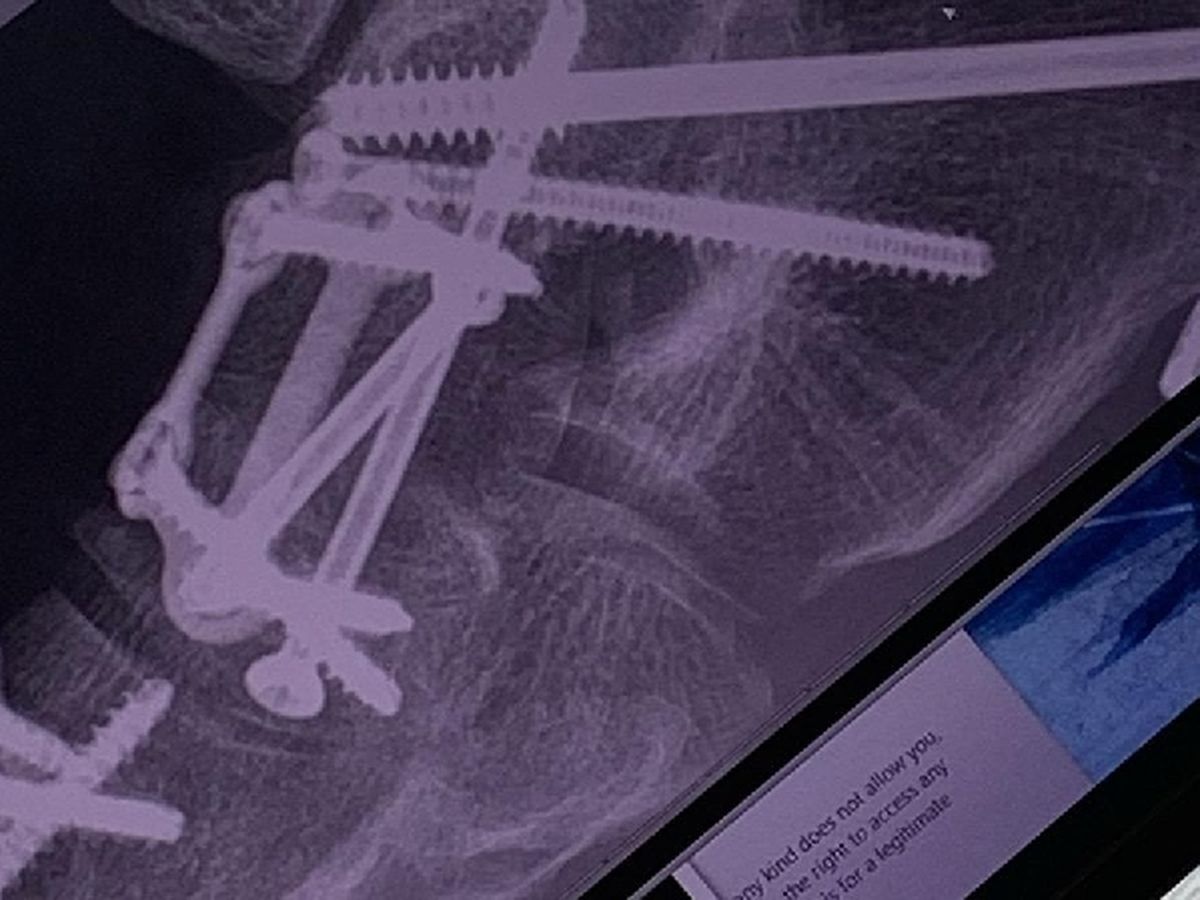

My daughter Maya was born with Cerebral Palsy. When she was younger, she used a walker, but as she got older was able to walk without it. Just like her Dad she's always been very independent, and strong willed. If you told her she couldn't do it, then she was just more determined to show you she could. She refused to get SSI, and was determined to make her own way in life. She got a job, got her own apartment, and furnished it the way she wanted it furnished. As much as I offered, she would never let me buy her anything unless it was her birthday or Christmas. Well starting last July, she was in so much pain walking, that they had to do reconstructive surgery on both her feet. She lost her job, and apt. Now she's in a wheelchair learning how to walk again. We currently have her in a hotel while im working overseas until I can get back, and find her a place to stay. I had her applied for SSI so she can get some type of income, and amazingly, she was denied. I'm over the moon pissed off. How do you deny someone who was born disabled disability??!!?? I know people who are perfectly fine that get disability, and someone who was born with cerebral palsy, is in a wheelchair, and cannot walk is denied because the doctor says she MIGHT be able to walk again in 6-8 months?!? Are you fucking kidding me?!? So what does she do for the next 6-8 months??? So now I have to pay for a lawyer on top of the hotel? Do I have to go John-Q?!!? Currently my ex, her siblings, and me are holding her down but damn, what if she was on her own? I remember when I was living in Brooklyn, Her and her sister came to visit me one summer, and we were at the Saint Marks Church. St Marks had this big step out front, and I could see her out of the corner of my eye. I knew she was going to take that step, and that was ready to catch her. She took it, and I caught her. As long as I'm around, I won't let her fall.